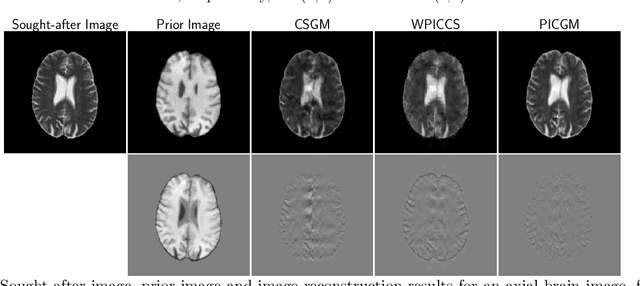

Computed medical imaging systems require a computational reconstruction procedure for image formation. In order to recover a useful estimate of the object to-be-imaged when the recorded measurements are incomplete, prior knowledge about the nature of object must be utilized. In order to improve the conditioning of an ill-posed imaging inverse problem, deep learning approaches are being actively investigated for better representing object priors and constraints. This work proposes to use a style-based generative adversarial network (StyleGAN) to constrain an image reconstruction problem in the case where additional information in the form of a prior image of the sought-after object is available. An optimization problem is formulated in the intermediate latent-space of a StyleGAN, that is disentangled with respect to meaningful image attributes or "styles", such as the contrast used in magnetic resonance imaging (MRI). Discrepancy between the sought-after and prior images is measured in the disentangled latent-space, and is used to regularize the inverse problem in the form of constraints on specific styles of the disentangled latent-space. A stylized numerical study inspired by MR imaging is designed, where the sought-after and the prior image are structurally similar, but belong to different contrast mechanisms. The presented numerical studies demonstrate the superiority of the proposed approach as compared to classical approaches in the form of traditional metrics.